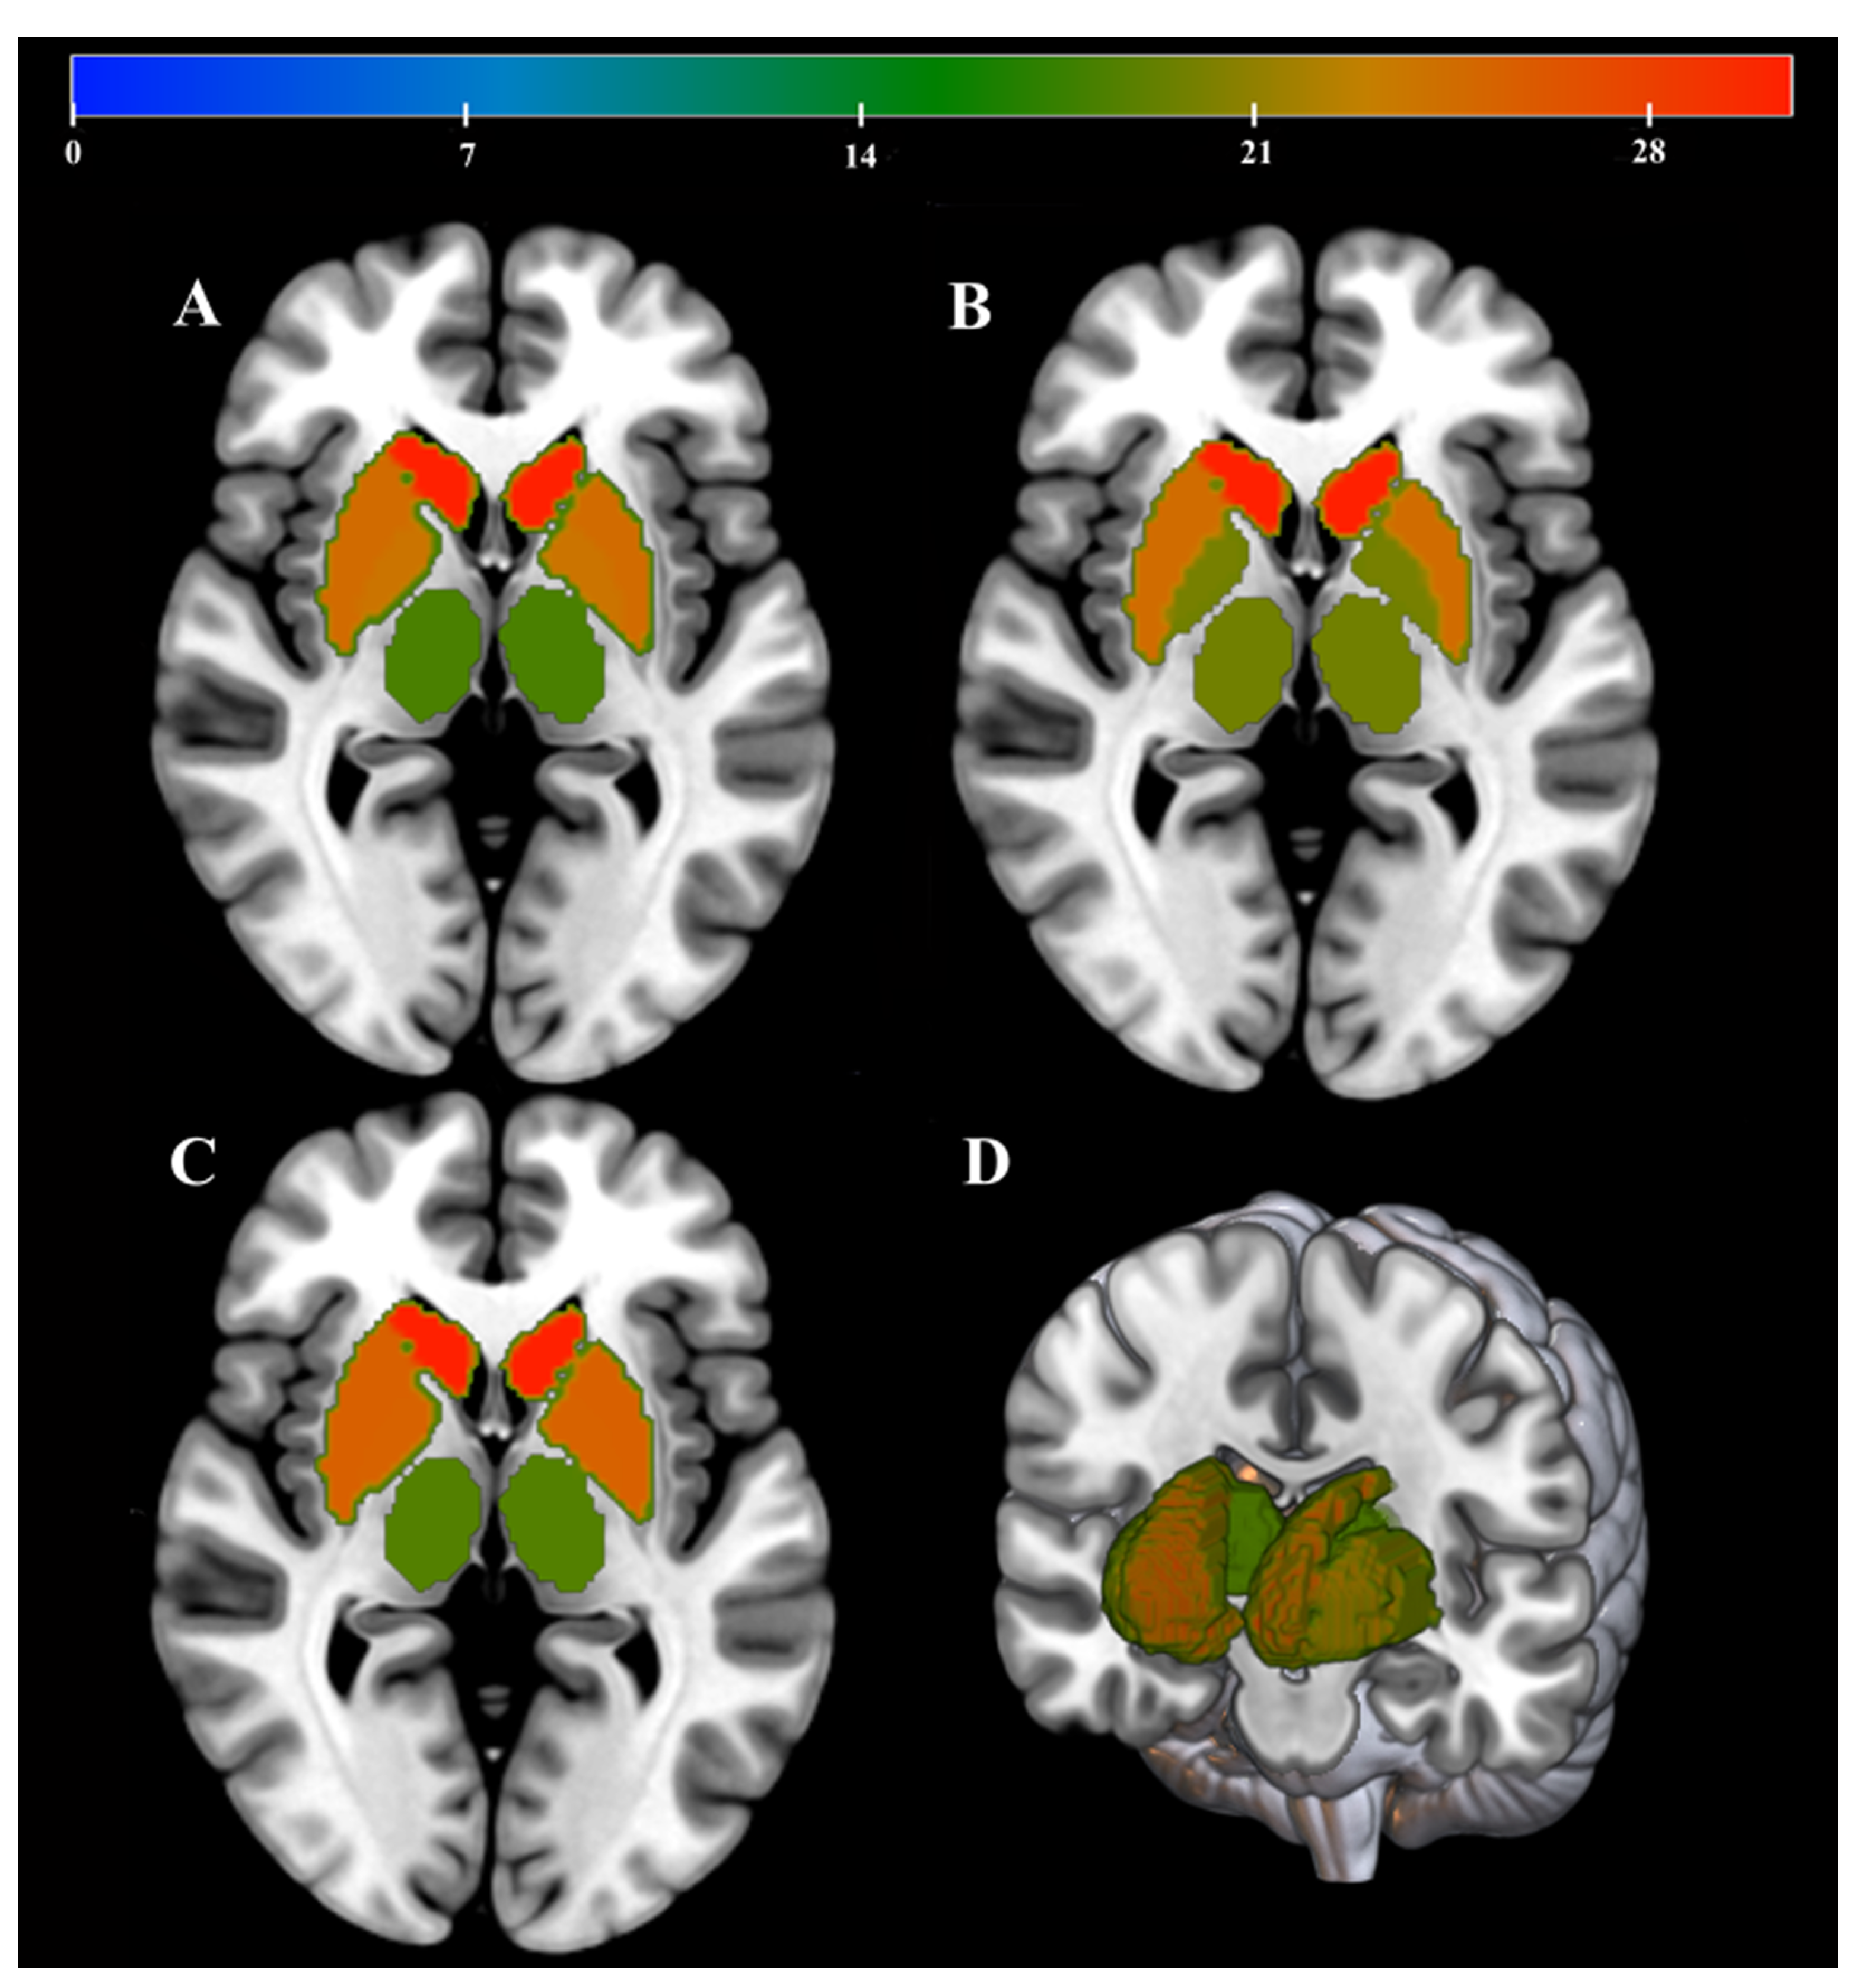

| Region | Weights (%) | Cluster Size (vox) | |

|---|---|---|---|

| QSV | CN | 30.53 | 1666 |

| PT | 25.54 | 2061 | |

| GP | 25.33 | 573 | |

| TH | 18.6 | 2083 | |

| FA | CN | 31.38 | 1666 |

| PT | 25.34 | 573 | |

| GP | 24.58 | 2061 | |

| TH | 18.7 | 2083 | |

| MD | CN | 32.21 | 1666 |

| PT | 25.89 | 573 | |

| GP | 21.11 | 2083 | |

| TH | 20.79 | 2061 |